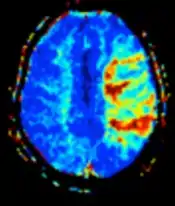

| Diffusion weighted (DWI) | Conventional | DWI | Measure of Brownian motion of water molecules.[78] | High signal within minutes of cerebral infarction (pictured).[79] | ![]() |

| Apparent diffusion coefficient | ADC | Reduced T2 weighting by taking multiple conventional DWI images with different DWI weighting, and the change corresponds to diffusion.[80] | Low signal minutes after cerebral infarction (pictured).[81] | ![]() | |